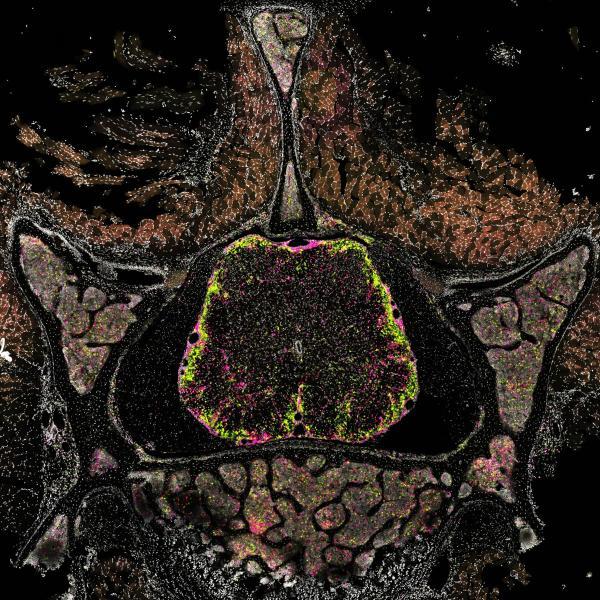

SV2A-PET imaging uncovers cortical synapse loss in multiple sclerosis

October 2025 – Gray matter damage and cortical lesions drive progression in people with multiple sclerosis (PwMS). In a new study, the Kerschensteiner lab collaborated with our clinical team and the group of Matthias Brendel at the Department of Nuclear Medicine to show that positron emission...